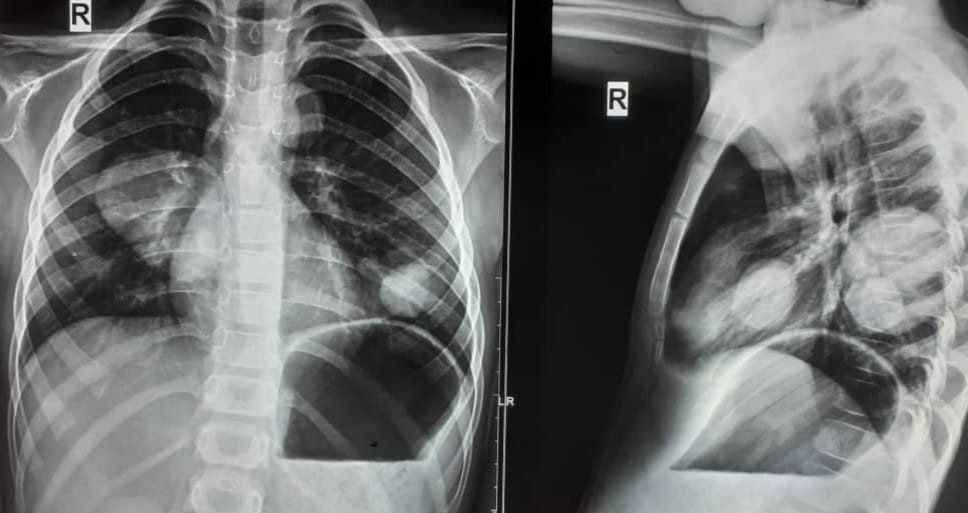

"6 жаштагы бала эч жери оорубай, кокустан көкүрөгү кыйшык болуп ортопед дарыгерге кайрылышат. Рентгенге тартса эки өпкөсүнөн, анан боорунда эхинококкоз оорусу чыгат. Кээде чоңоюп жарылып кетиши мүмкүн. Ошон үчүн балдарыңарды жылына 2 жолудан текшертип тургула. Бул оору азайбай эле, көбөйүп жатат. Кээде жарылып, өтө чоң болгондо, же ириңдегенде кайрылып жатышат", - деп жазган дарыгер.